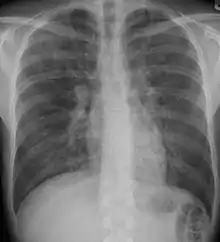

X-ray and CT (radiography and computed tomography)

Chest radiography is usually the first test to detect interstitial lung diseases, but the chest radiograph can be normal in up to 10% of patients, especially early in the disease process.[13][14]

High-resolution CT of the chest is the preferred modality and differs from routine CT of the chest. Conventional (regular) CT chest examines 7–10 mm slices obtained at 10 mm intervals; high resolution CT examines 1–1.5 mm slices at 10 mm intervals using a high-spatial-frequency reconstruction algorithm. The HRCT therefore provides approximately 10 times more resolution than the conventional CT chest, allowing the HRCT to elicit details that cannot otherwise be visualized.[13][15]

Radiologic appearance alone, however, is not adequate and should be interpreted in the clinical context, keeping in mind the temporal profile of the disease process.[13]